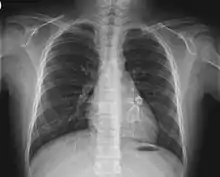

Cardiac

Heart complications are the most important aspect of Kawasaki disease, which is the leading cause of heart disease acquired in childhood in the United States and Japan.[31] In developed nations, it appears to have replaced acute rheumatic fever as the most common cause of acquired heart disease in children.[15] Coronary artery aneurysms occur as a sequela of the vasculitis in 20–25% of untreated children.[52] It is first detected at a mean of 10 days of illness and the peak frequency of coronary artery dilation or aneurysms occurs within four weeks of onset.[48] Aneurysms are classified into small (internal diameter of vessel wall <5 mm), medium (diameter ranging from 5–8 mm), and giant (diameter > 8 mm).[31] Saccular and fusiform aneurysms usually develop between 18 and 25 days after the onset of illness.[15]

Even when treated with high-dose IVIG regimens within the first 10 days of illness, 5% of children with Kawasaki disease develop at the least transient coronary artery dilation and 1% develop giant aneurysms.[53][54][55] Death can occur either due to myocardial infarction secondary to blood clot formation in a coronary artery aneurysm or to rupture of a large coronary artery aneurysm. Death is most common two to 12 weeks after the onset of illness.[15]

Many risk factors predicting coronary artery aneurysms have been identified,[21] including persistent fever after IVIG therapy,[56][57] low hemoglobin concentrations, low albumin concentrations, high white-blood-cell count, high band count, high CRP concentrations, male sex, and age less than one year.[58] Coronary artery lesions resulting from Kawasaki disease change dynamically with time.[3] Resolution one to two years after the onset of the disease has been observed in half of vessels with coronary aneurysms.[59][60] Narrowing of the coronary artery, which occurs as a result of the healing process of the vessel wall, often leads to significant obstruction of the blood vessel and the heart not receiving enough blood and oxygen.[59] This can eventually lead to heart muscle tissue death, i.e., myocardial infarction (MI).[59]

MI caused by thrombotic occlusion in an aneurysmal, stenotic, or both aneurysmal and stenotic coronary artery is the main cause of death from Kawasaki disease.[61] The highest risk of MI occurs in the first year after the onset of the disease.[61] MI in children presents with different symptoms from those in adults. The main symptoms were shock, unrest, vomiting, and abdominal pain; chest pain was most common in older children.[61] Most of these children had the attack occurring during sleep or at rest, and around one-third of attacks were asymptomatic.[15]

Valvular insufficiencies, particularly of mitral or tricuspid valves, are often observed in the acute phase of Kawasaki disease due to inflammation of the heart valve or inflammation of the heart muscle-induced myocardial dysfunction, regardless of coronary involvement.[59] These lesions mostly disappear with the resolution of acute illness,[62] but a very small group of the lesions persist and progress.[63] There is also late-onset aortic or mitral insufficiency caused by thickening or deformation of fibrosed valves, with the timing ranging from several months to years after the onset of Kawasaki disease.[64] Some of these lesions require valve replacement.[65]